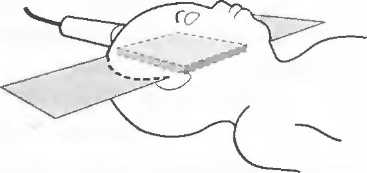

3. Ультразвуковые исследования в педиатрии. Для детей необходим датчик с частотой 5 МГц с глубиной фокусировки на 5-7 см. При исследовании мозга новорожденного используется секторный датчик с частотой 7,5 МГц с глубиной фокусировки на 4-5 см (этот датчик также используется для исследования яичек и структур шеи у взрослых).